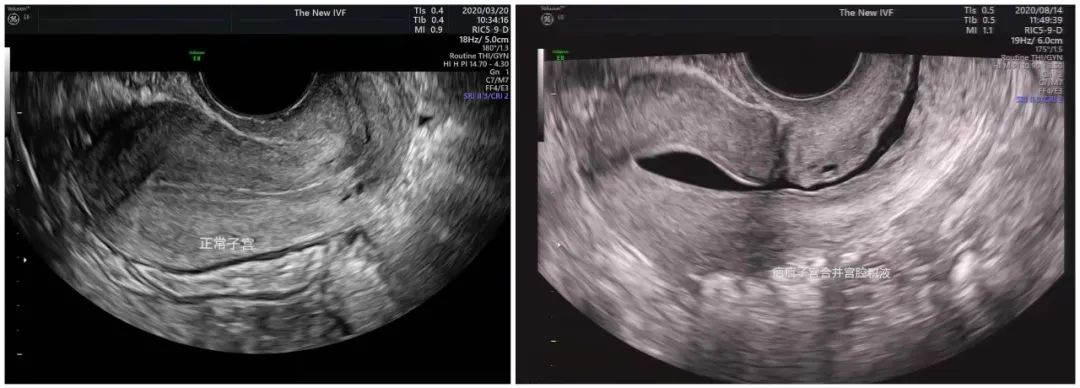

▲左图示:正常子宫;右图示:疤痕子宫合并宫腔积液

宫腔积液简单说,就是子宫腔内存在一定量液体。其中包括生殖道分泌的生理性积液,如月经血,和病理性的积液,如炎性渗出液、积血、积脓等。

积液有可能影响子宫内膜的微环境,对怀孕的结局产生影响。